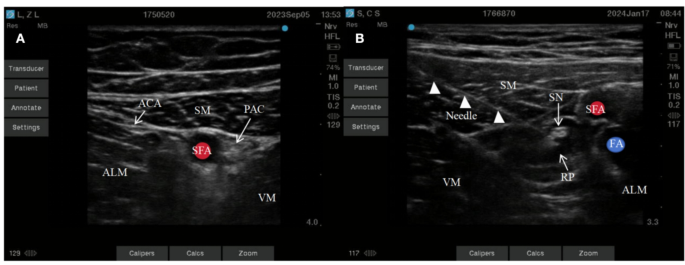

The patient lies down, with legs slightly separated, and the affected limb is slightly abducted and externally rotated to fully expose the medial thigh area. Select a linear array probe and perform sterile processing. Place the probe horizontally on the inner thigh, perpendicular to the femur. Adjust the direction and angle of the probe to locate the medial edge of the sartorius muscle and the medial edge of the long adductor muscle. At the junction of the tendons of these two muscles, observe the tendinous plate structure of the adductor canal, which is marked as the entrance of the adductor canal. Move the ultrasound probe downwards and outwards by about 1–2 cm to clearly display the sonographic images of the sartorius muscle, long adductor muscle, and medial femoral muscle. Between these three muscles, the pulsating sonographic image of the superficial femoral artery can be observed. On the lateral side of the superficial femoral artery, the adductor canal structure can be seen (Fig. 1A), which is marked as the proximal end of the adductor canal .Using the in-plane puncture technique, a 22G nerve block needle is inserted into the skin from the lateral end of the probe. Slowly advancing towards the target nerve, the needle tip passes through the sartorius muscle, the sub-sartorius space, and the adductor magnus muscle membrane. Once there is no blood or air upon withdrawal, local anesthetic can be injected. Under ultrasound, the diffusion of local anesthetic solution within the adductor canal can be observed (Fig. 1B).

Ultrasound image of the proximal saphenous nerve in the adductor canal (A), Ultrasound image of needle insertion in the proximal plane of the adductor canal (B). ALM, adductor longus muscle; ACA, adductor canal aponeurosis; SM, sartorius muscle; SFA, superficial femoral artery; PAC, proximal adductor canal; VM, vastus medialis; SN, saphenous nerve; RP, ropivacaine; FA, femoral vein.